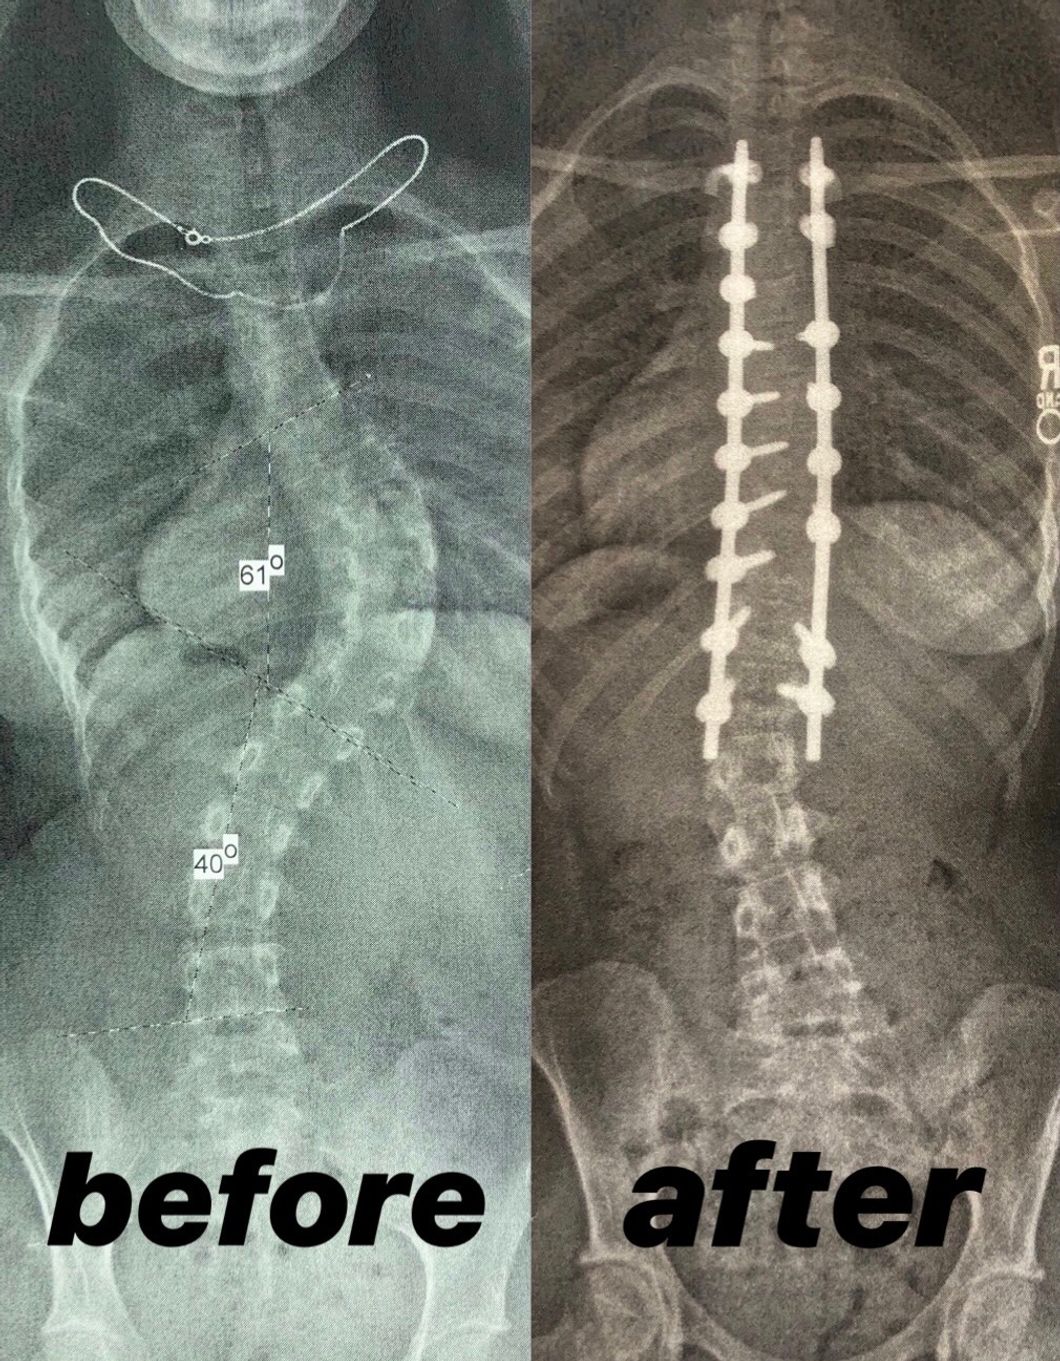

Once I discovered that spinal fusion surgery was not only an option but also recommended for severe scoliosis like mine, I finally saw a way out of the future I thought I couldn't control. One day, I could actually be happy in my own skin. One day, I could actually be pain-free. I decided to schedule my surgery for the nearest available date. Once I caught a glimpse of those possibilities, I never looked back.

My surgery experience went as smoothly as it could have, and I recovered quickly. Three weeks after my operation, I went back to school. Three more weeks later, I went back to most of my regular activities. Since my 6-week post-op appointment, I haven't returned to the hospital.